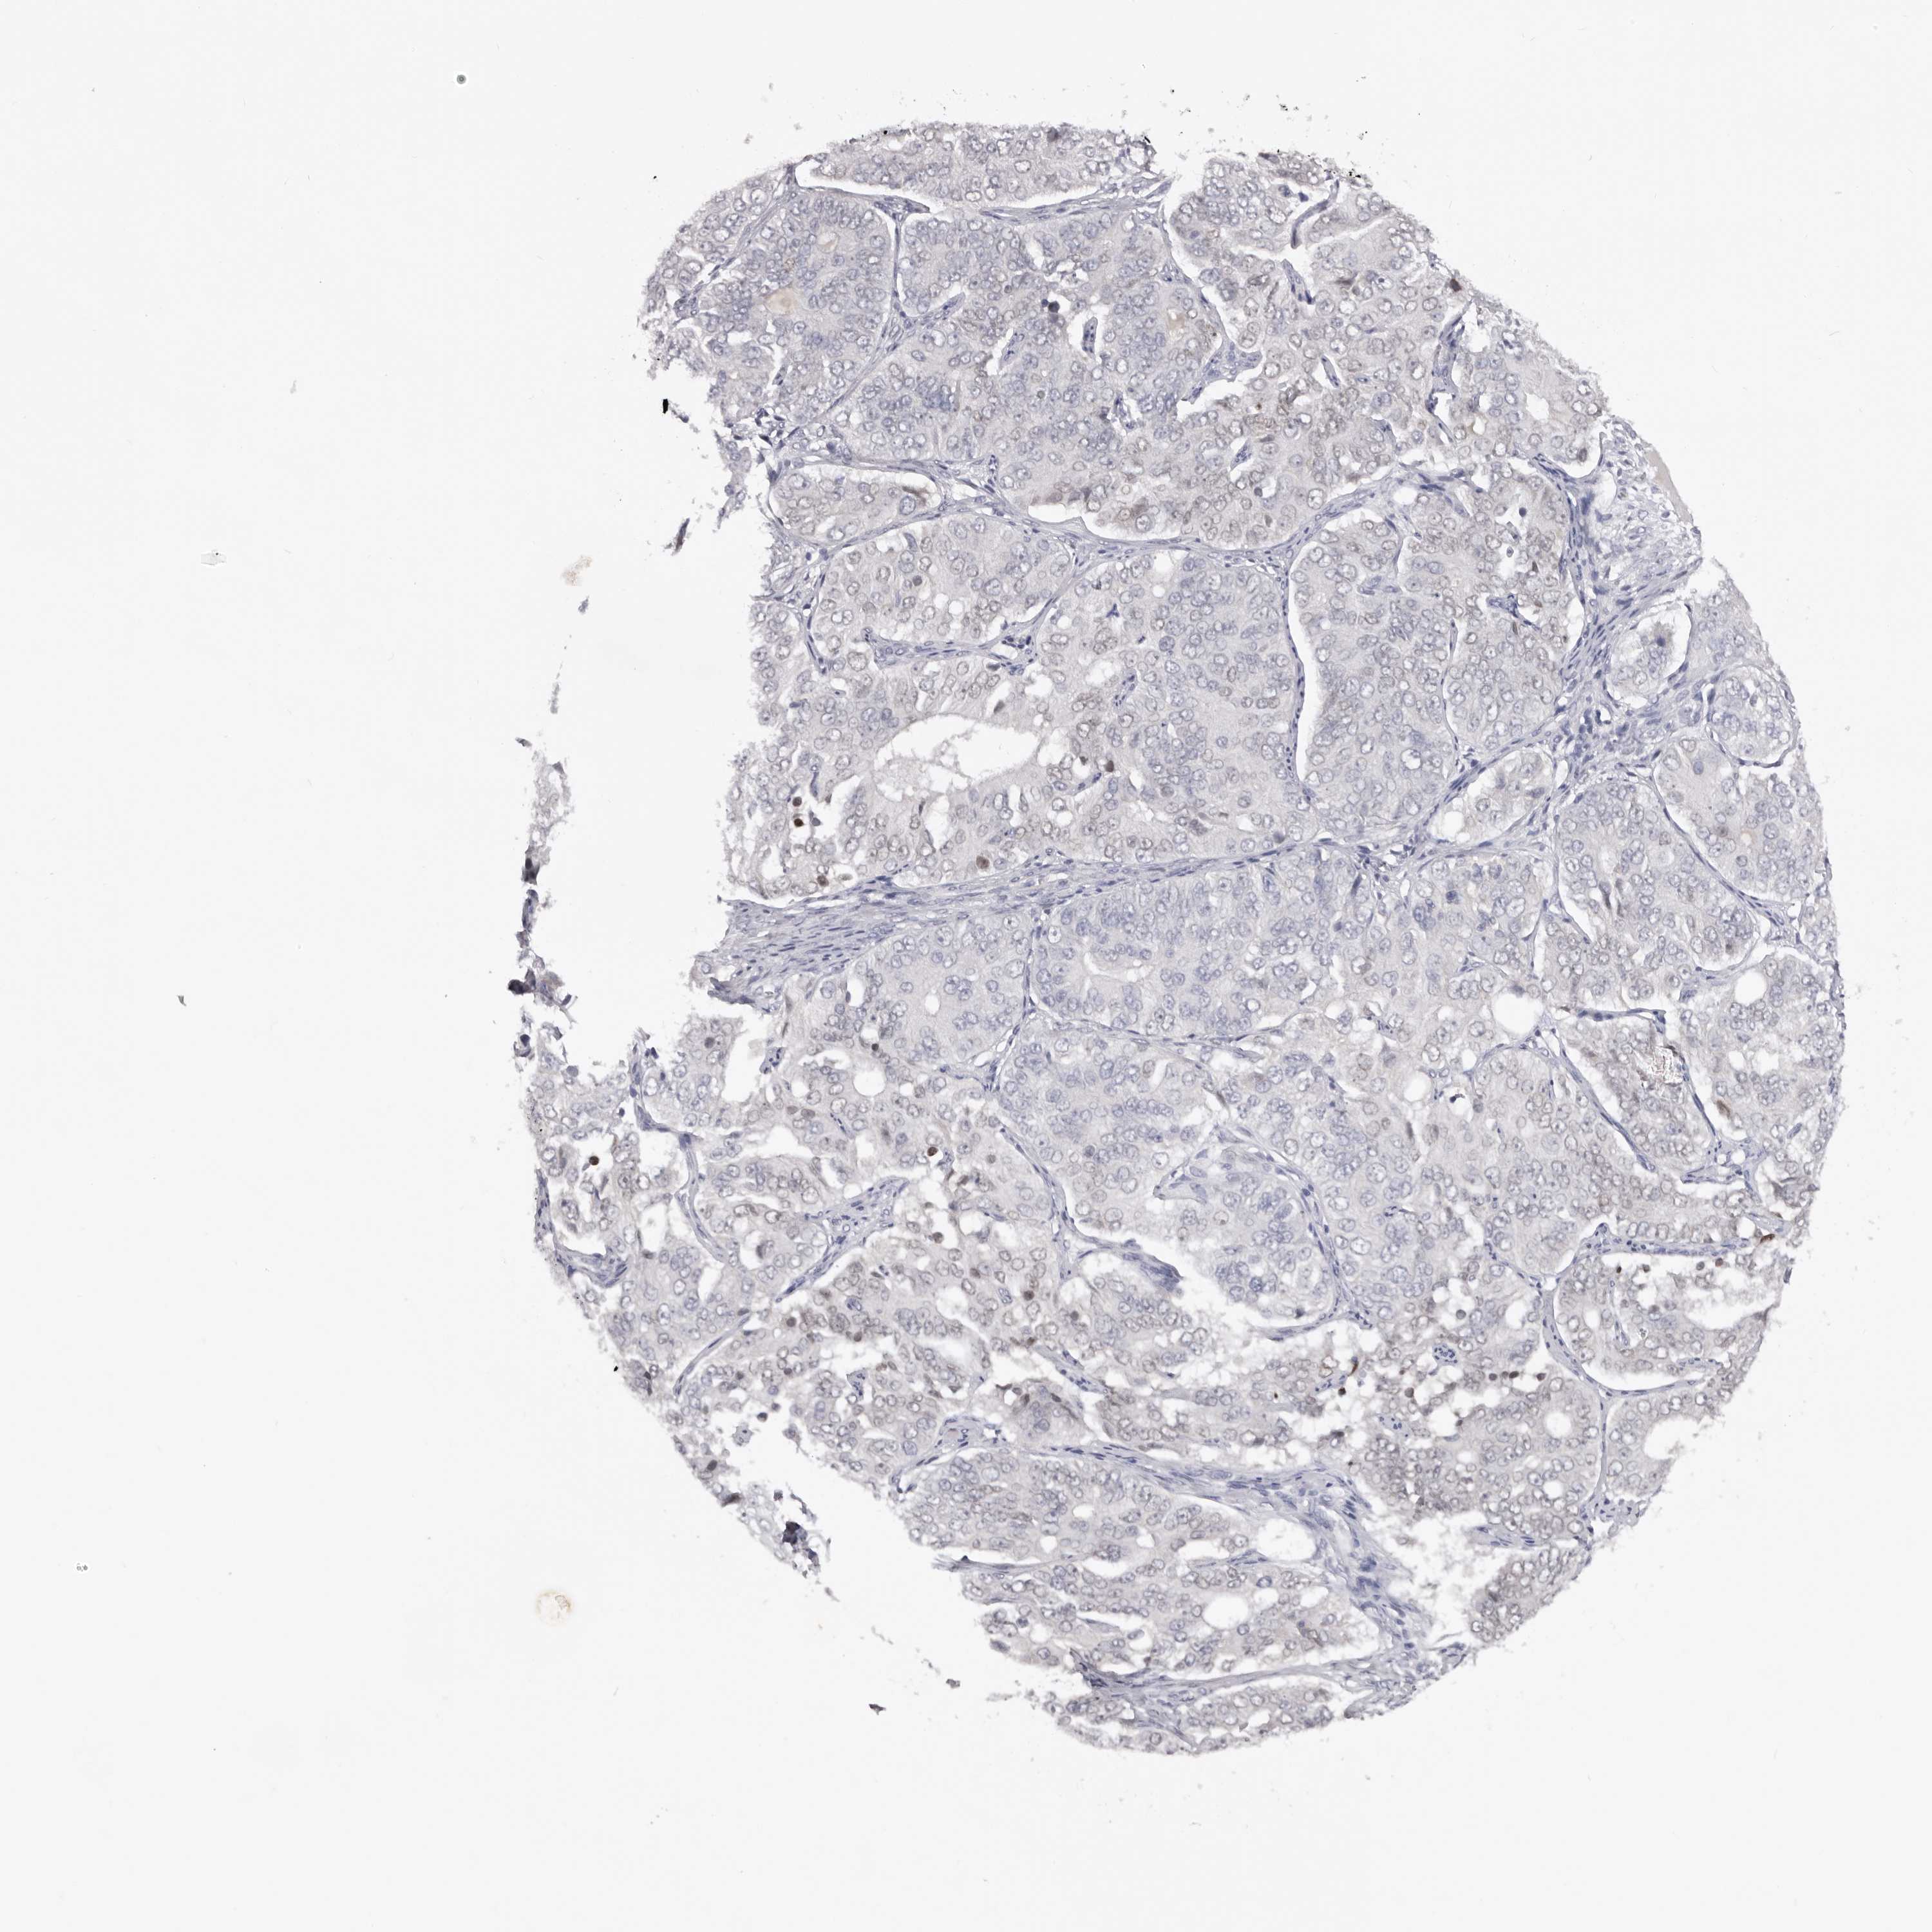

OVARIAN CANCER - Protein expressioni

A mouse-over function shows sample information and annotation data. Click on an image to view it in a full screen mode. Samples can be filtered based on level of antibody staining by selecting one or several of the following categories: high, medium, low and not detected. The assay and annotation is described here.

Note that samples used for immunohistochemistry by the Human Protein Atlas do not correspond to samples in the TCGA dataset.

Antibody stainingi

Antibody staining in the annotated cell types in the current human tissue is reported as not detected, low, medium, or high, based on conventional immunohistochemistry profiling in selected tissues. This score is based on the combination of the staining intensity and fraction of stained cells.

Each image is clickable and will lead to virtual microscopy that enables deeper exploration of all samples and also displays staining intensity scores, fraction scores and subcellular localization as well as patient and tissue information for each sample.

Antibody HPA027134

Antibody HPA027150

Antibody HPA029859

Antibody CAB022343

Cystadenocarcinoma, serous, NOS

Carcinoma, endometroid

Cystadenocarcinoma, mucinous, NOS

Carcinoma, NOS